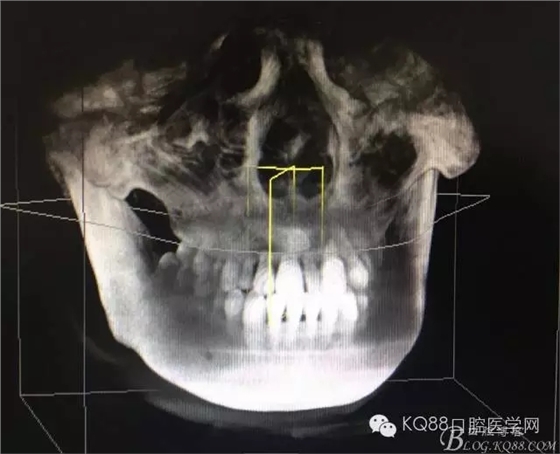

圖5.三維重建影像: